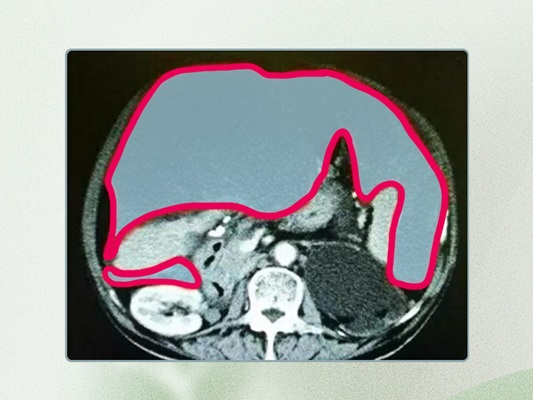

腹膜假黏液瘤的典型临床表现包括腹围增大、腹胀以及食欲减退等。多数情况下,是在进行体检或其他疾病的腹部CT检查时,发现了腹腔内异质性或水样密度的黏液性物质而得以诊断。

腹膜假黏液瘤手术治疗叫肿瘤细胞减灭术加腹腔热灌注化疗。

肿瘤切除包括多个方面:首先需要完整切除大网膜和小网膜;其次,需要切除肝脏表面及其实质表面的腹膜,以及膈肌表面的腹膜;有时候还需要切除脾脏及其区域的腹膜,甚至包括脾脏本身;接下来是切除盆腔的腹膜,必要时还需切除直肠,对于女性患者,可能还需要一并切除子宫、两侧卵巢以及直肠;此外,阑尾部位也需要切除;最后,还需要切除小肠系膜表面的肿瘤。

腹腔肿瘤清理干净之后,然后再进行热灌注化疗,国际标准的热灌注化疗是用43℃的生理盐水加化疗药物,比如顺铂、5-氟尿嘧啶、奥沙利铂、紫杉类药物等,在43℃的温度下,高浓度的化疗药物在腹腔内持续循环60-90分钟,彻底冲洗掉残留的肿瘤细胞。